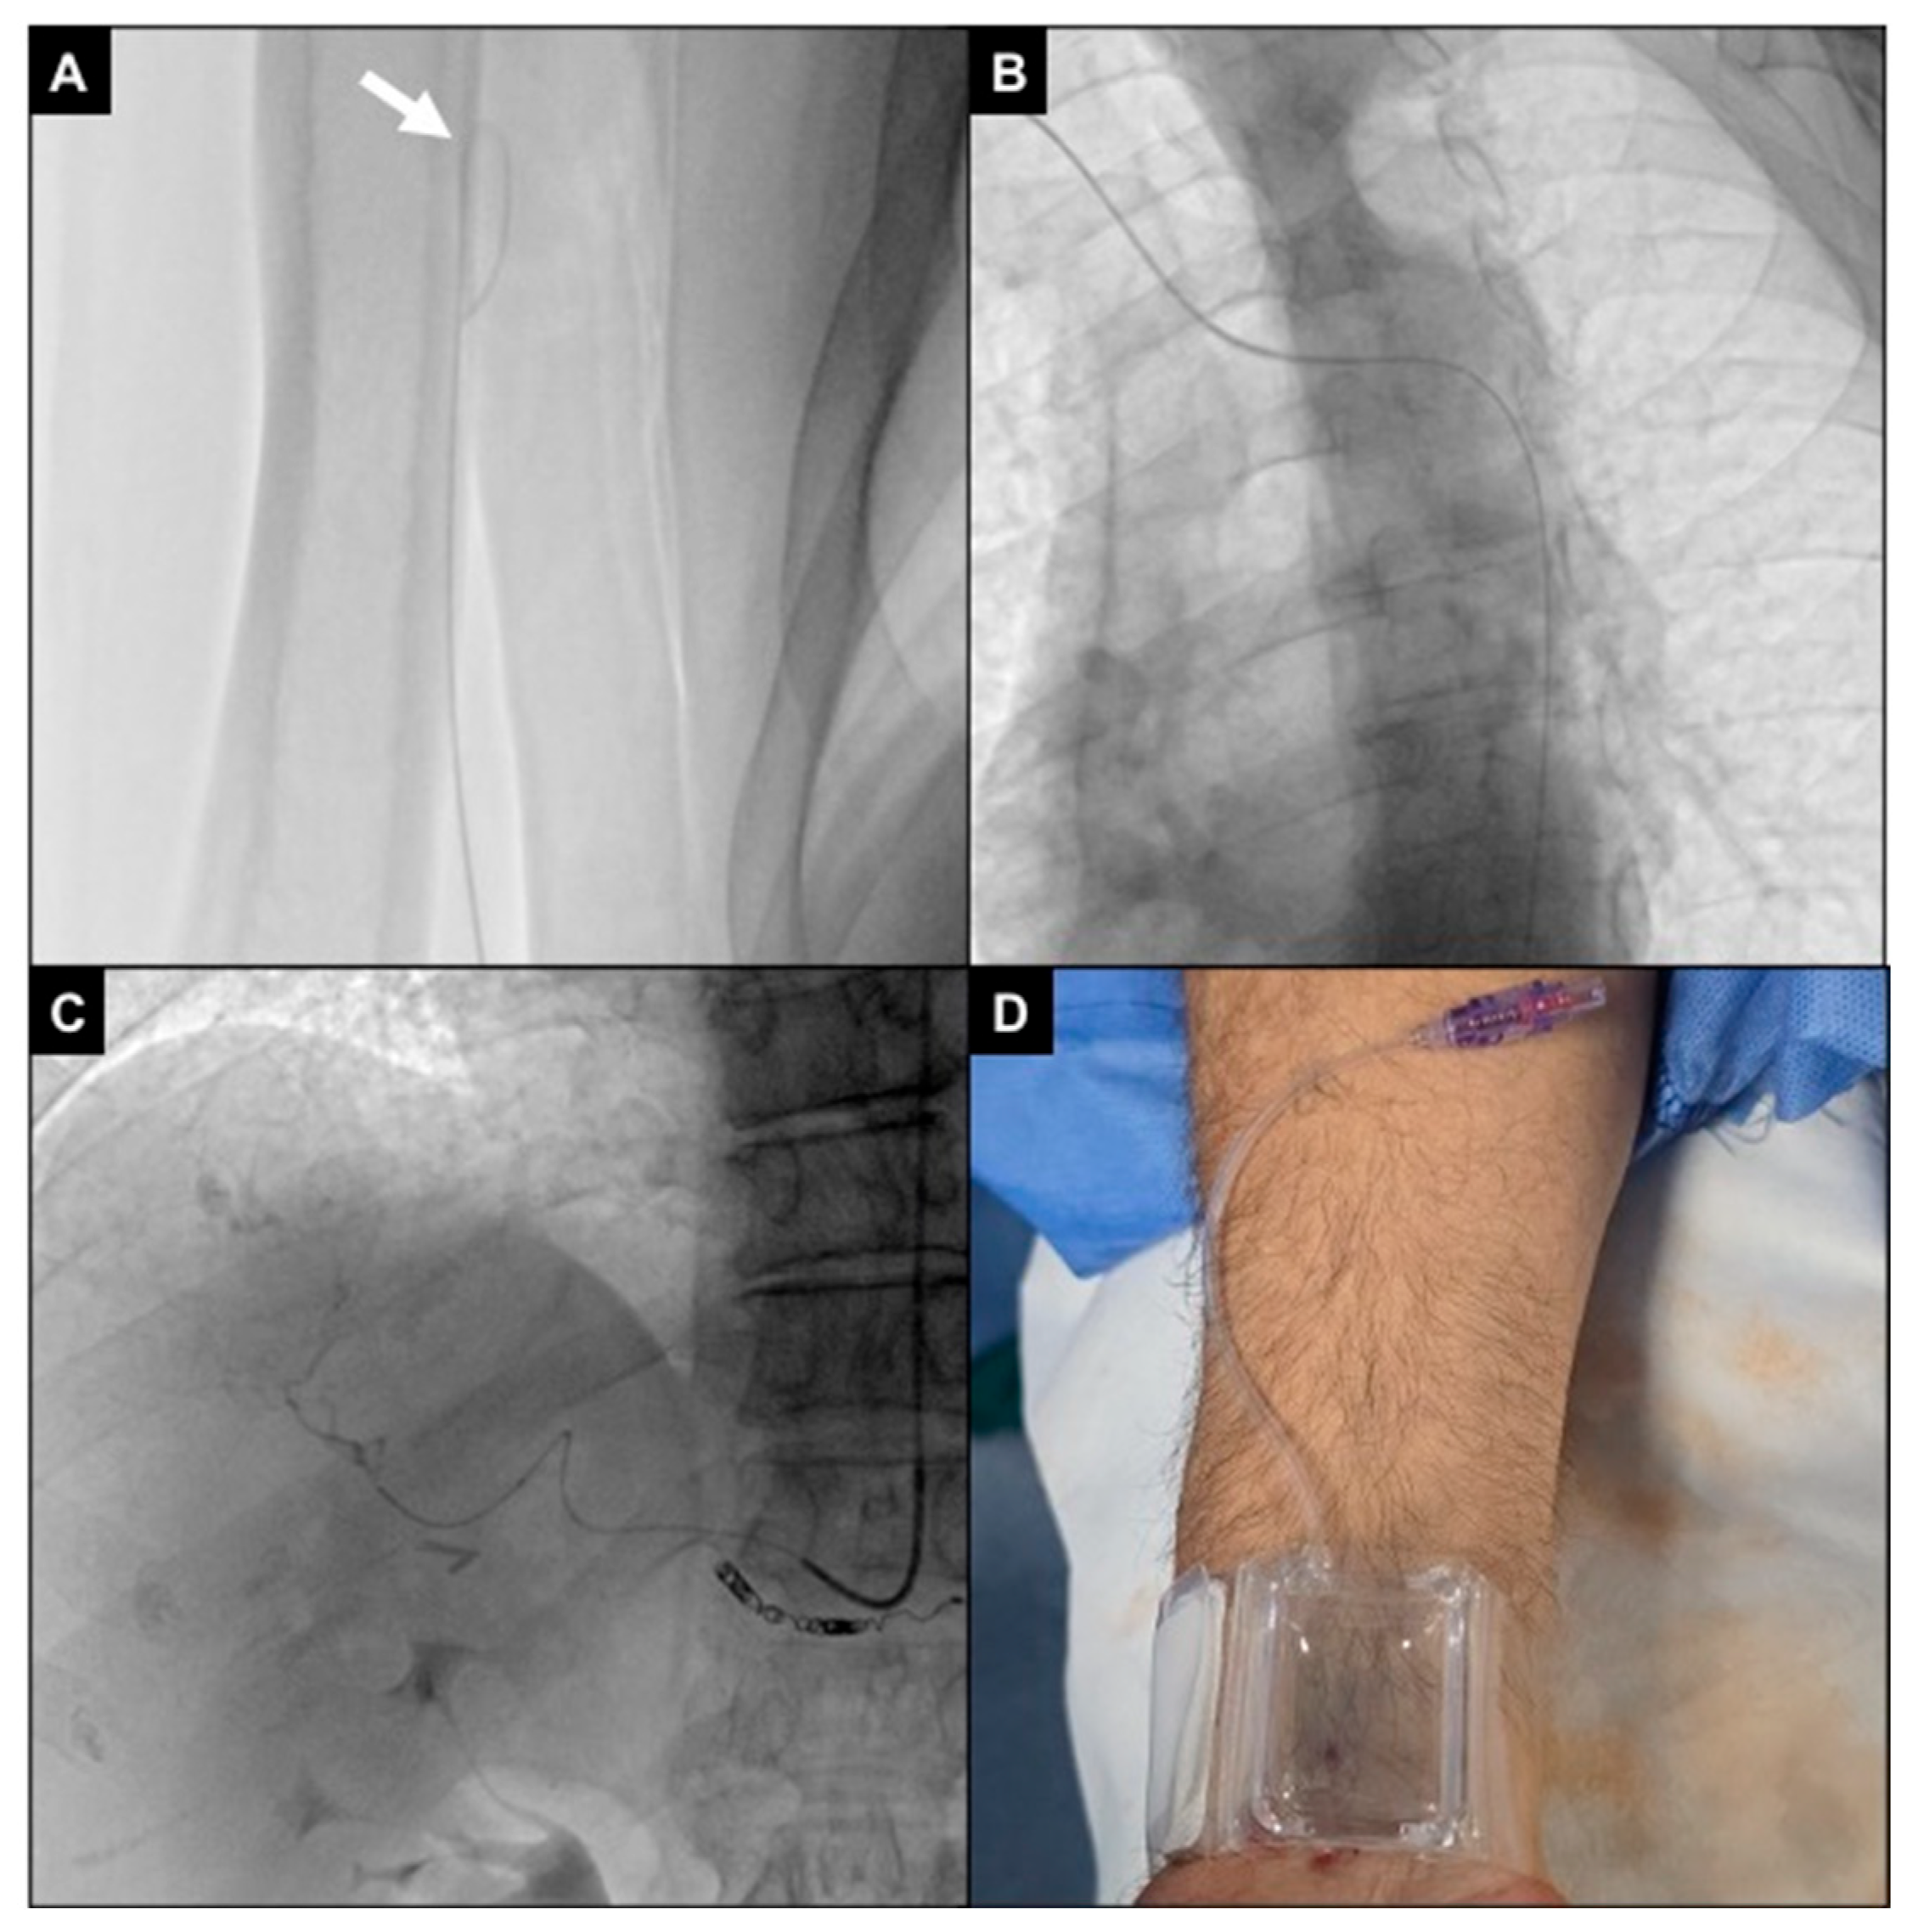

2.4. Procedures

- Gayed, A.; Yamada, R.; Bhatia, S.; Fischman, A.; Heran, M.K.S.; Himes, E.A.; Klass, D.; Patel, S.; Schiro, B.J.; Walker, T.G.; et al. Society of interventional radiology quality improvement standards on radial artery access. J. Vasc. Interv. Radiol. 2021, 32, 761.e1–761.e21. [Google Scholar] [CrossRef]

- Rivera, K.; Fernández-Rodríguez, D.; Ferreiro, J.L. Distal radial access in interventional cardiology: Technique, pitfalls and recommendations. Cardiovasc. Diagn. Ther. 2025, 15, 665–683. [Google Scholar] [CrossRef]